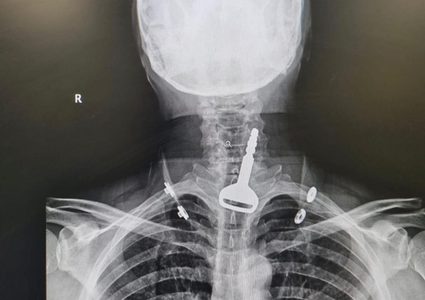

جراح سعودي ينقذ حياة أربعيني ابتلع مفتاح سيارته